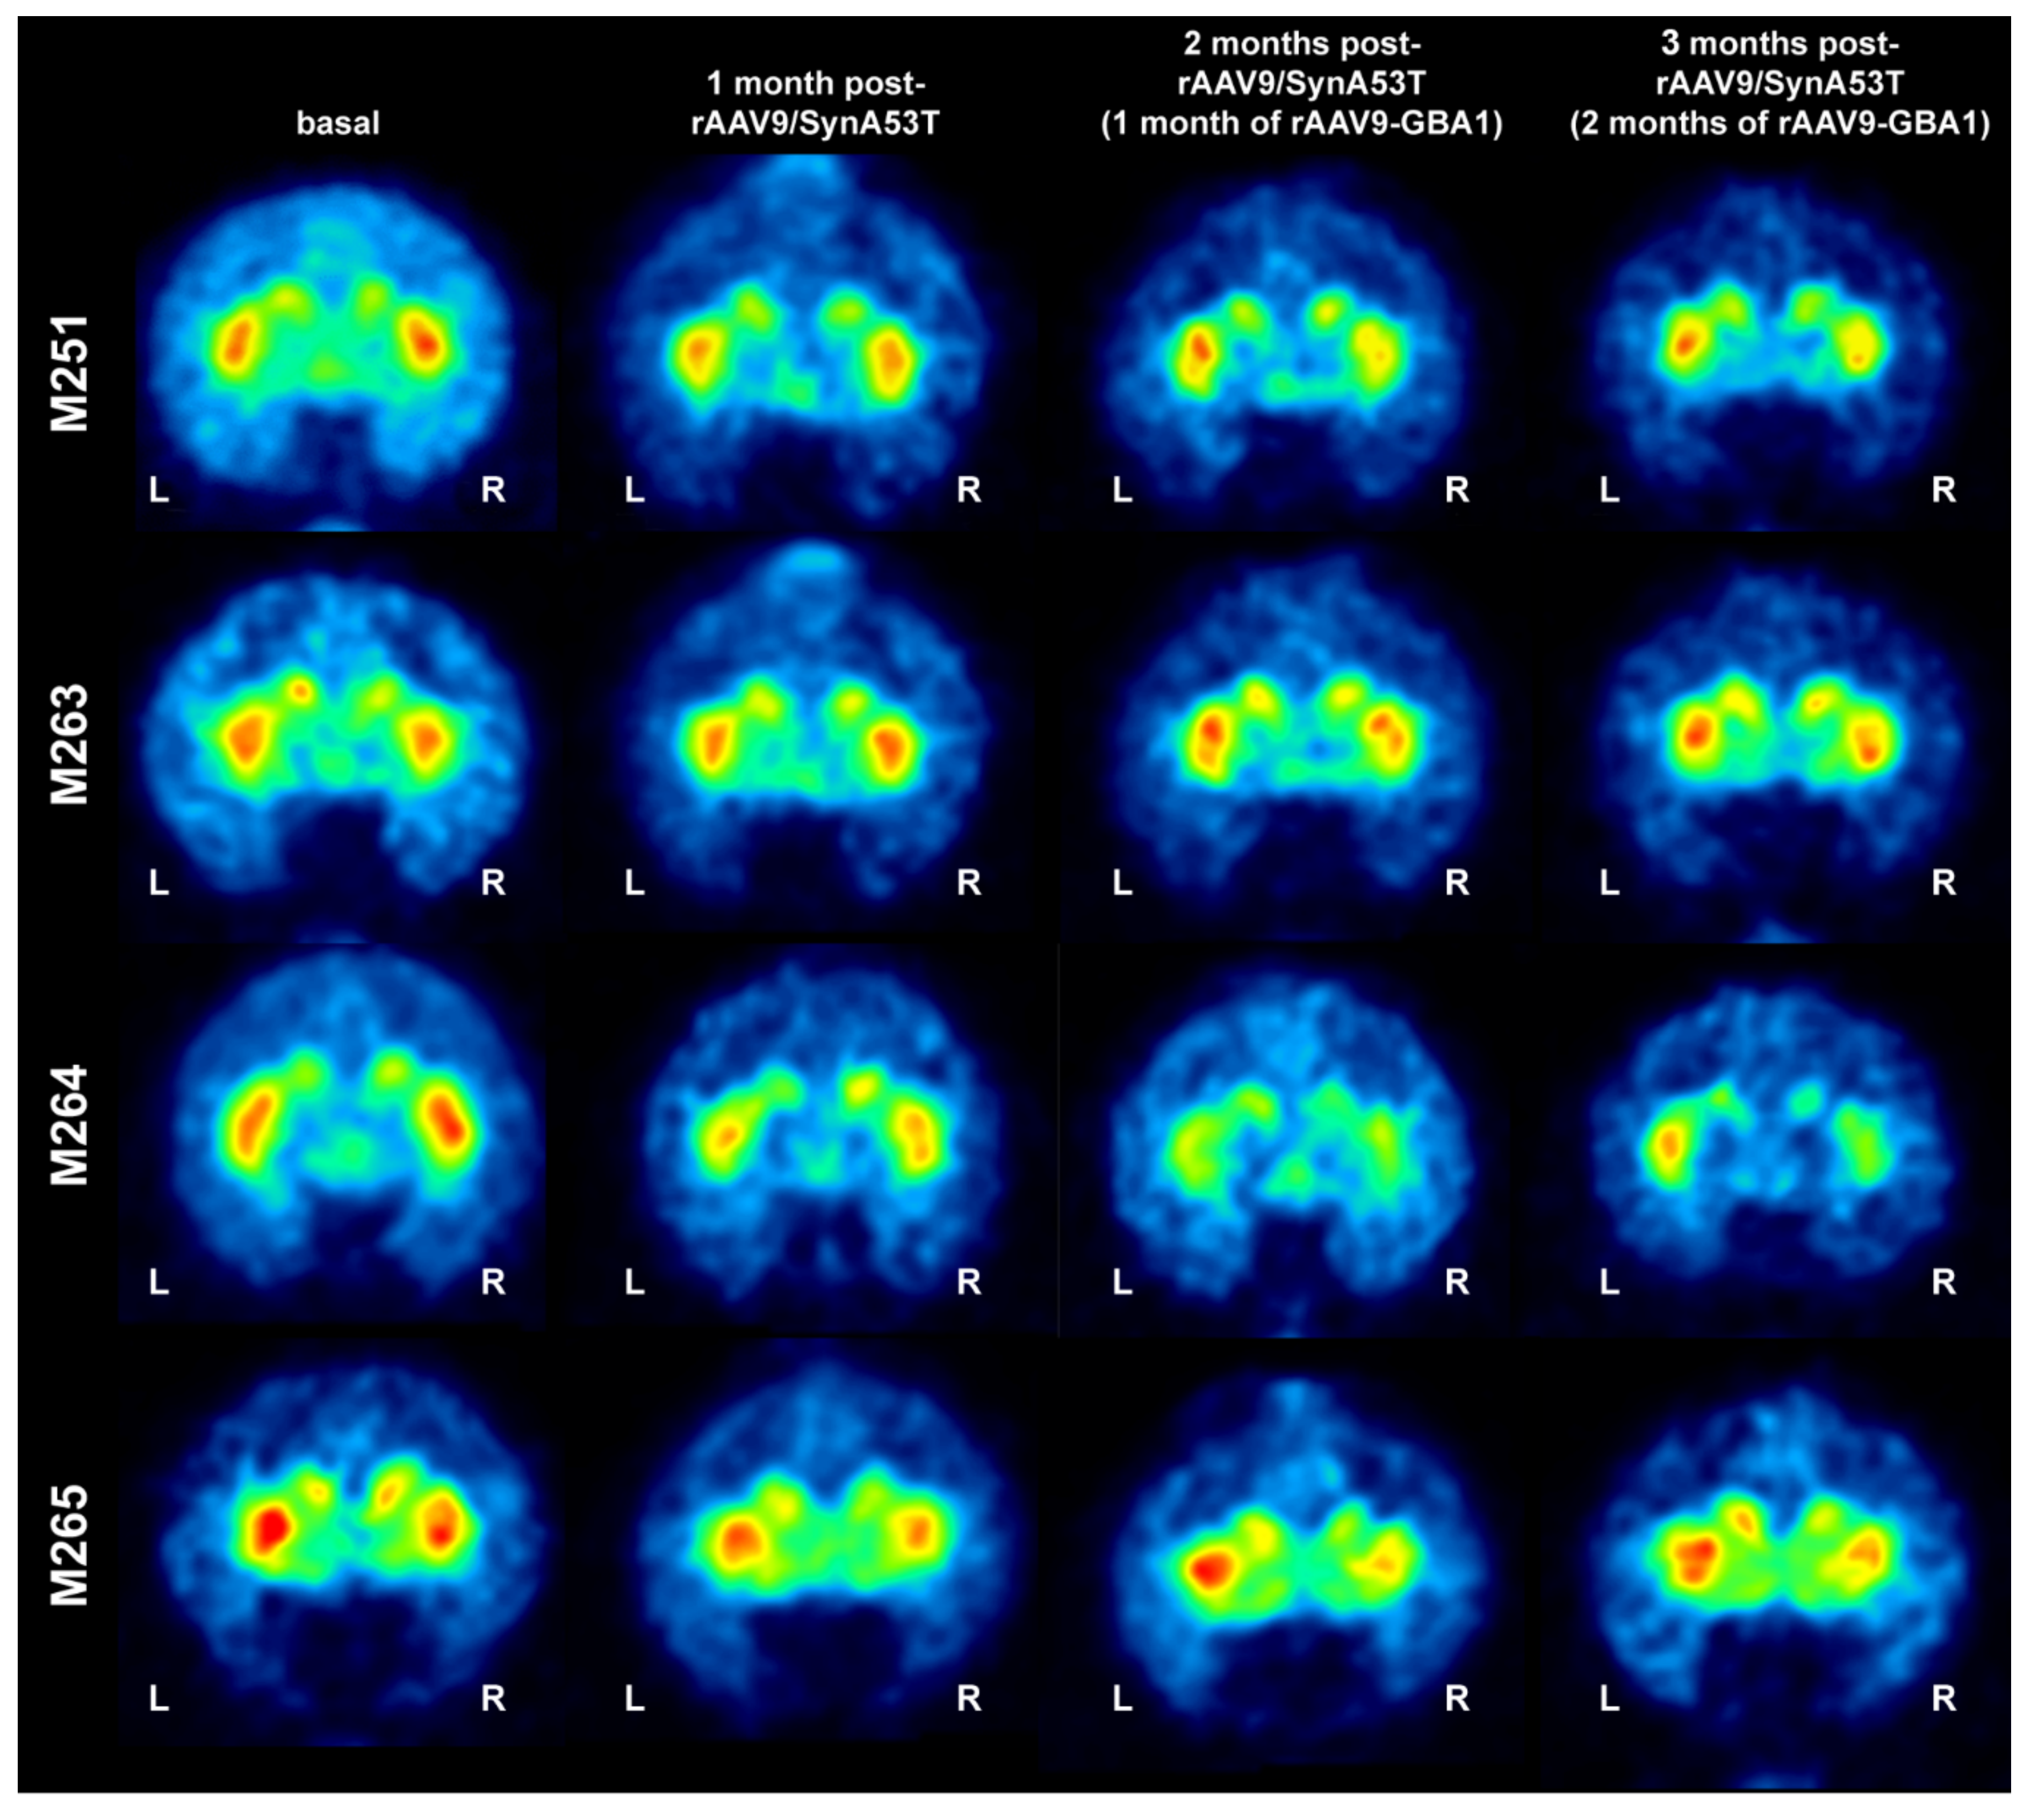

The density of dopaminergic innervation of the caudate and putamen nuclei was assessed in vivo by neuroimage MicroPET scanning using the radiotracer 11C-dihydrotetrabenazine (11C-DTBZ; a selective VMAT2 ligand). Scans were performed at baseline and 4, 8, and 12 weeks post-injection of rAAV9-SynA53T. All animals showed a bilateral reduction in the 11C-DTBZ-binding potential four weeks after delivery of rAAV9-SynA53T, although to a variable interindividual extent. Four weeks after delivery of rAAV9-GBA1 (left SNpc) and rAAV-null (right SNpc), 3 out of 4 animals showed an asymmetrical pattern of 11C-DTBZ uptake that was confirmed at eight weeks’ time point for all animals (e.g., 12 weeks post-bilateral injection of rAAV9-SynA53T). However, although there was a clear trend supporting left vs. right asymmetries in radiotracer uptake (Figure 3) when compared to baseline levels, observed differences failed to reach statistical significance.

Figure 3.

MicroPET follow-up of NHPs. Representative coronal images taken at the level of the post-commissural caudate and putamen nuclei for all the 4 NHPs included in the study. MicroPET scans with 11C-DTBZ were taken at baseline, and 1, 2 and 3 months post-bilateral delivery of rAAV9-SynA53T. Compared to baseline radiotracer uptake levels, a bilateral decline is observed in all animals one month post-injection of rAAV9-SynA53T. One month later (e.g., 2 months posttreatment with rAAV9-SynA53T and 1 month post-injection of rAAV9-GBA1 in the left SNpc and rAAV9-null in the right SNpc), an asymmetrical pattern of radiotracer uptake is noticed in all animals with the only exception of M263. MicroPET scans were repeated one month later (3 months of rAAV9-SynA53T, including 2 months of rAAV9-GBA1 and rAAV-null), evident left vs. right differences in radiotracer uptake were observed in all animals. When compared to baseline levels, observed differences with a follow-up of 3 months failed to reach statistical significance.